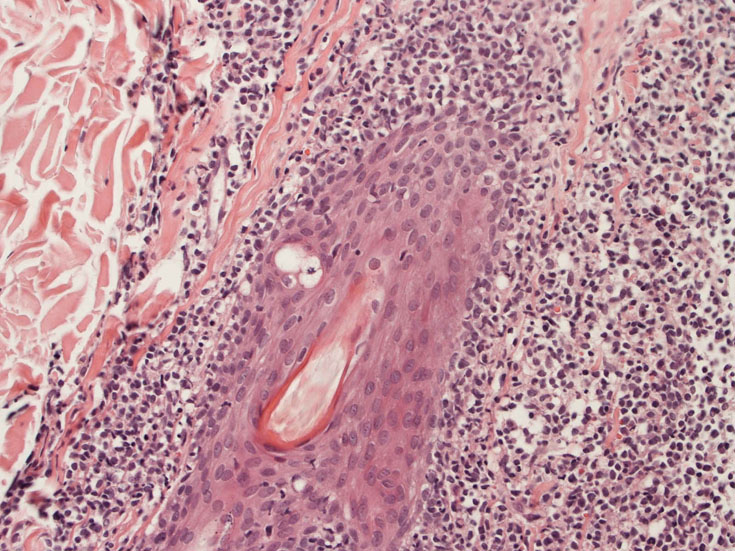

罹患リンパ節の基本構造は消失し腫瘍細胞のびまん性増殖で置換されている。非腫瘍性の小リンパ球(CD3+, CD4/8+)が濾胞様に散在して残る(Fig.01)。不整型または類円形の明るい核をもつmedium-sizeのリンパ球様細胞が密に増殖している。細胞質は乏しい(Fig.02)。CD68陽性macrophageが多く混在する部分が認められた(Fig.03)。

residualfollicle01.jpg

Fig.01Fig.02Fig.03